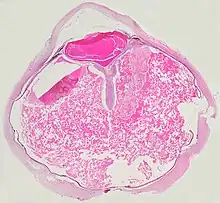

Pathologic findings

Grossly, retinal detachment and yellowish subretinal exudate containing cholesterol crystals are commonly seen.

Microscopically, the wall of retinal vessels may be thickened in some cases, while in other cases the wall may be thinned with irregular dilatation of the lumen.[10] The subretinal exudate consists of cholesterol crystals, macrophages laden with cholesterol and pigment, erythrocytes, and hemosiderin.[11] A granulomatous reaction, induced by the exudate, may be seen with the retina.[12] Portions of the retina may develop gliosis as a response to injury.